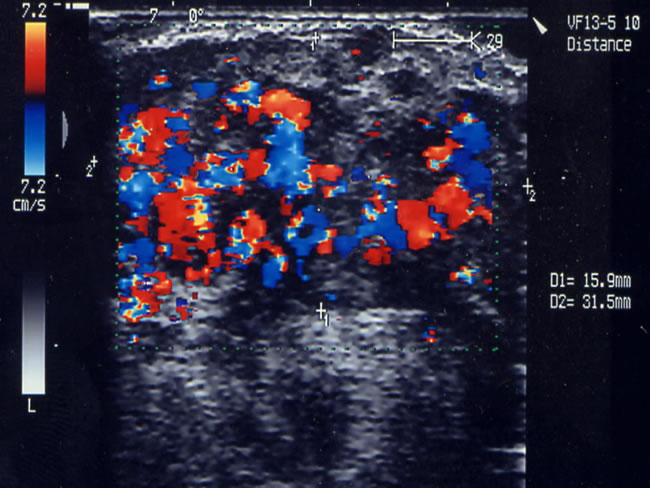

Doppler CW Figura 8 b

Immagine Ecocolordoppler | Figura 9 a